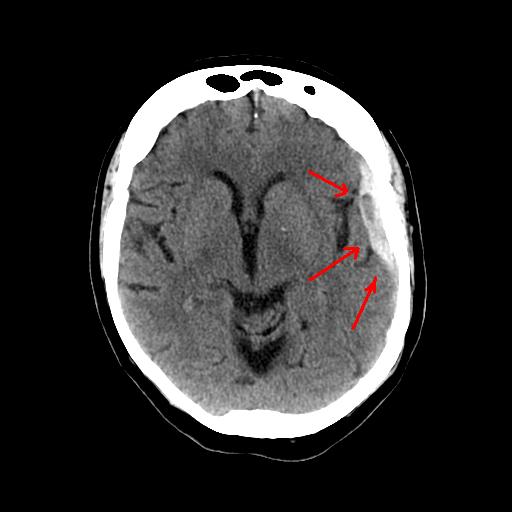

На первом этапе разработчики решили сфокусироваться на использовании системы для идентификации внутримозговых кровоизлияний, с которыми связано 10% всех инсультов, и просматривании сканов грудной клетки.